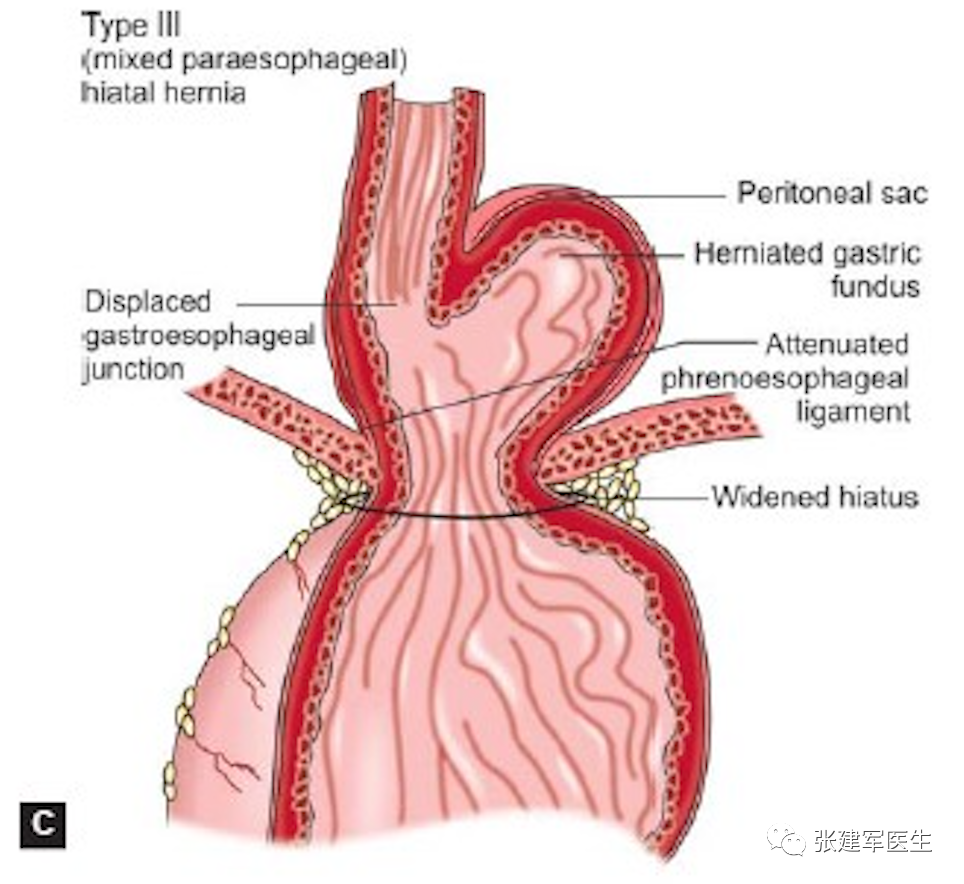

食管裂孔疝主要有两种类型:滑动性食管裂孔疝和食管旁食管裂孔疝。大多数为滑动型食管裂孔疝,即1 型。其他三种类型均为食管旁疝。

III型(混合型食管裂孔疝) – 它是 I 型和 II 型的组合,其特征是胃大弯和胃食管结合部均进入胸腔。